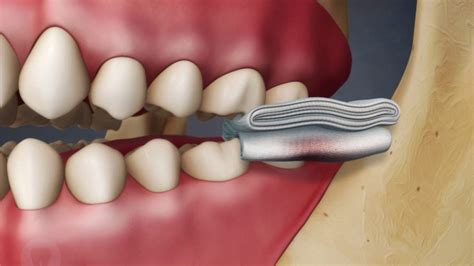

• biting cheek when eating

• cheek bite in adults

• biting inside cheek

• stop cheek biting overnight

• how to stop chewing cheeks

• chewing inside of cheek